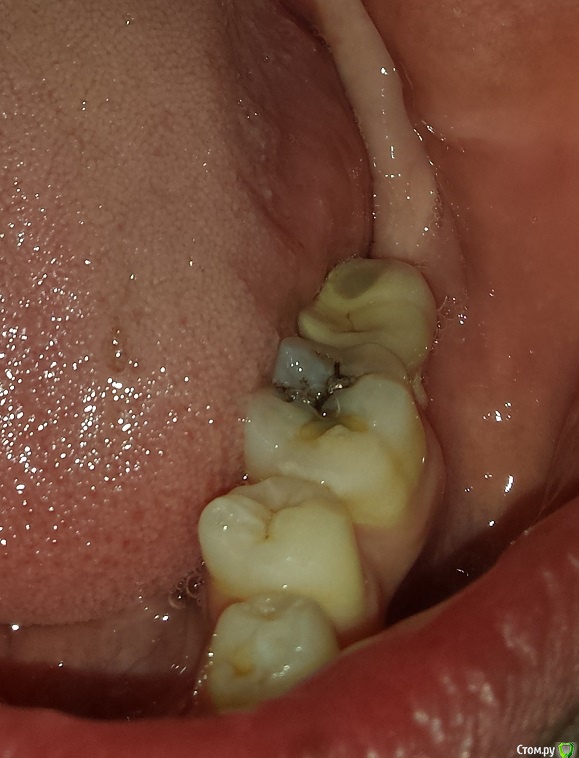

permico Опубликовано 23 августа, 2017 Поделиться Опубликовано 23 августа, 2017 (изменено) Добрый день.Примерно год назад во Франции мне были установлены 2 импланта на нижнюю челюсть взамен отсутствующих семерок (восьмерки были удалены еще раньше), т.е.37 и 47 зубов. Система Implant Direct (США), тип Swish plus, длина 10 мм. диаметр 5.7 и 4.1 мм. Врач уверил, что они являются репликой трансгингивальных Straumann Tissue Level с полированной шейкой и полностью совместимы. В общем, интегрировались они нормально, коронки он установил и я с ними проходил год без жалоб.Недавно сходил здесь в Москве к стоматологу, чтоб подкрутить винты на имплантах. Он все сделал и сказал, что нужно мне показаться хирургу-имплантологу так как они установлены скорее всего неправильно, забивается много пищи между коронками и десной (они сделаны с "балконом") и очень вероятно осложение в виде резорбции костной ткани. Сходил на консультацию к одному хирургу в Москве, он сказал, да действительно они неправильно установлены и им поможет только вынимайзинг с последующей установкой новых на то же место. Если сейчас не переустановлю, то через примерно пять лет их в любом случае придется вынимать, так как винт начнется оголяться, но уже кости будет меньше и будет труднее устанавливать новые.Хотел бы совета от специалистов на форуме, действительно ли они требуют удаления или можно сделать что-то другое. чтобы решить проблему.Прикладываю изображения (панорамный снимок после операции, недавние снимки имплантов, и фото их во рту, последние не очень хорошего качества, вечером могу попробовать переснять)Спасибо заранее, Борис Изменено 23 августа, 2017 пользователем permico Ссылка на комментарий

Art 7 Опубликовано 23 августа, 2017 Поделиться Опубликовано 23 августа, 2017 если хотите продлить жизнь имплантатам то надо выкрутить коронки, сделать пластику десны вокруг имплантатов и переделать коронки. это даст много лет жизни ималантатам 5 Ссылка на комментарий

brg Опубликовано 23 августа, 2017 Поделиться Опубликовано 23 августа, 2017 36, 46 нужно лечить. Ссылка на комментарий

Zlata-doctor Опубликовано 24 августа, 2017 Поделиться Опубликовано 24 августа, 2017 соседние с имплантами зубы нуждаются в лечении Ссылка на комментарий